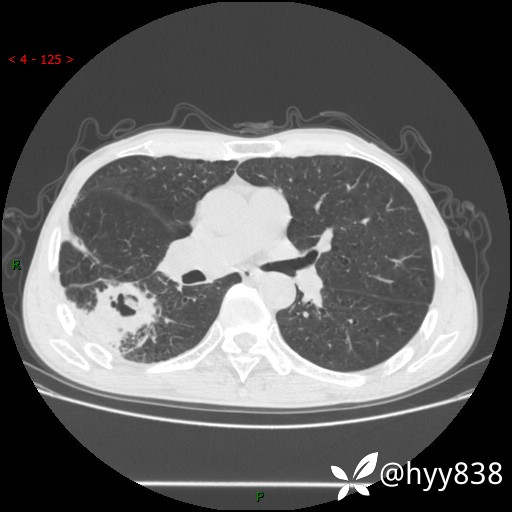

老年男性,肺团片状占位+体重下降,肿瘤 VS 真菌 VS 细菌,看看你的意见--结果公布~

简要病史:患者7天前无明显诱因出现咳嗽咳痰,咳绿色、褐色痰,吸烟后加重,伴心慌、胸闷,无畏寒发热,无头晕头痛,无鼻塞流涕,无痰中带血及咯血,无胸痛、呼吸困难,无全身酸痛,为求进一步诊治于我院就诊,门诊完善胸部CT提示“右下肺团片状影,考虑肿瘤?感染?”,门诊以“咳嗽待查”收住入院。 起病以来,患者精神、饮食、睡眠尚可,大、小便正常,体力下降,体重下降8斤。空腹血糖:6.42mmol/L。

辅助检查:CT

临床诊断:肿瘤?感染?

讨论:病变性质?

胸部CT平扫